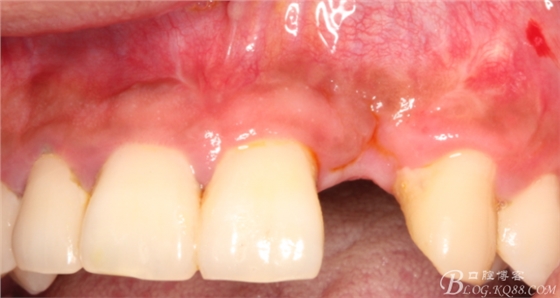

10天拆線一切正常,又過了兩周患者復(fù)診,自述期間無異常。口內(nèi)檢查,真的嚇了一跳,唇側(cè)鼓了個(gè)包,擠壓有白色分泌物溢出,絕對(duì)不是膿液,液體排除后,術(shù)區(qū)觸診空虛,外觀塌陷。這時(shí)候考研大夫的時(shí)刻到了,是先觀察一段時(shí)間再說?還是馬上進(jìn)行處理?我的回答是:馬上處理!如果你沒有及時(shí)處理,而是放患者回家觀察,那么接下來會(huì)發(fā)生如下情況:1.回家后患者家屬及親友會(huì)有很多你可以想象得到的討論;2.患者及家屬會(huì)對(duì)你產(chǎn)生不信任,勢(shì)必會(huì)到其他門診或醫(yī)院檢查,他院大夫會(huì)不會(huì)發(fā)表對(duì)你不利的言論;3甚至?xí)蚁嚓P(guān)法律界人士找你討要說法。

于是我果斷告知患者,手術(shù)失敗了,不能拖延,如不及時(shí)處理,炎癥繼續(xù)發(fā)展會(huì)很快波及鄰牙牙槽骨。患者接受我的建議。切開翻瓣,骨粉及生物膜消失了,骨吸收嚴(yán)重,幸運(yùn)的是,因?yàn)樘幚砑皶r(shí),鄰牙骨支持依然存在。